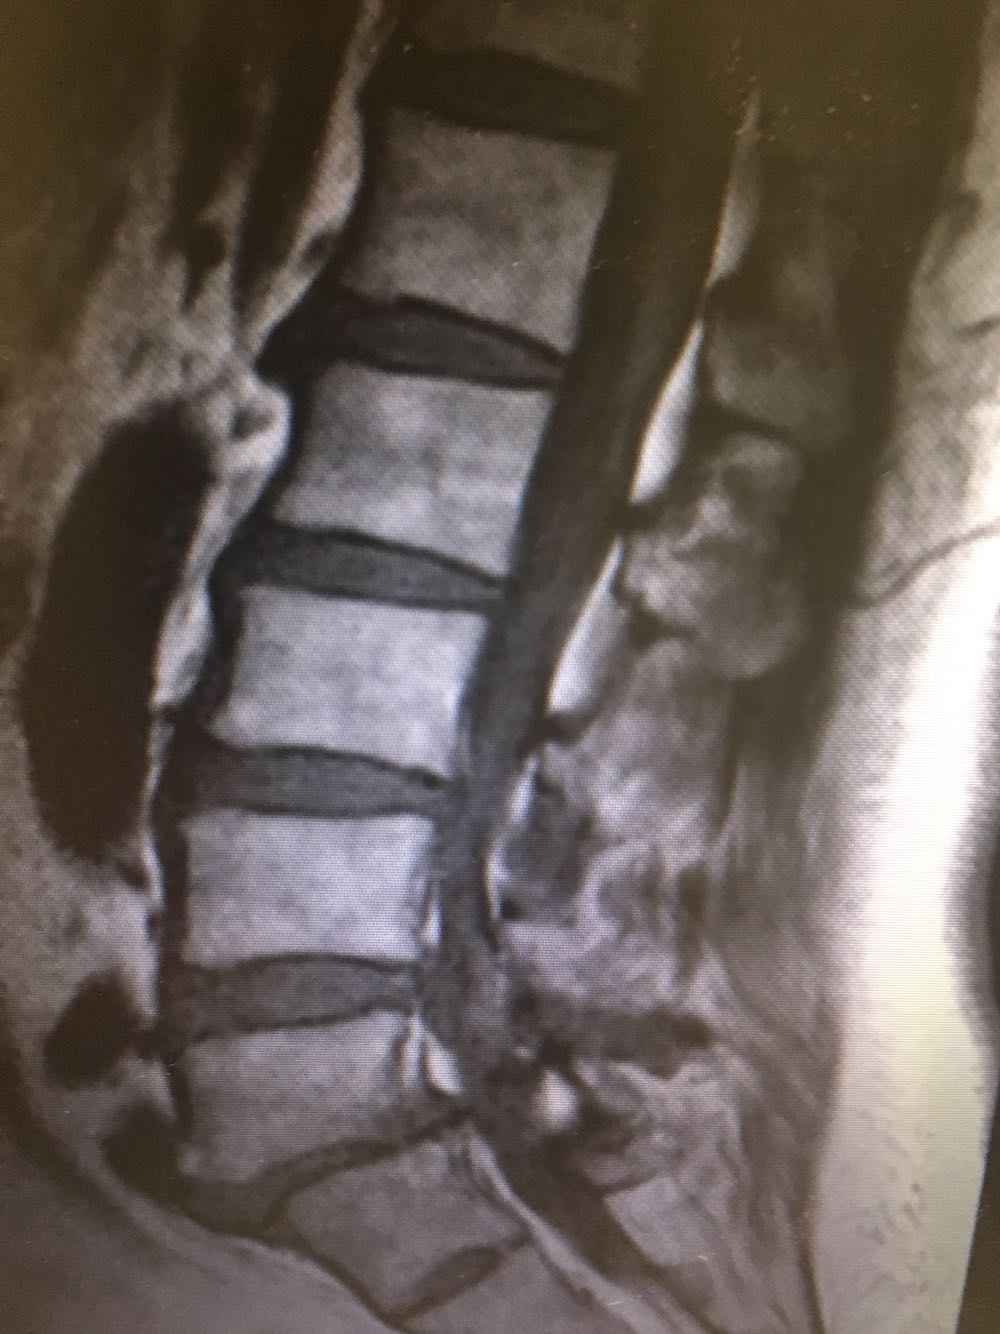

患者,女性,60岁 主诉:腰痛伴下肢疼痛2年 现病史:患者于2年前无明显诱因下出现腰痛伴左侧下肢疼痛,休息后缓解,未予重视,半年前出现双下肢外侧疼痛,酸胀伴跛行,休息后稍缓解,病程中否认头晕头痛、恶心呕吐等不适,遂至我院门诊就诊,查腰椎X片示:L5椎体向前轻度滑脱,伴退行性变,椎间隙变窄,现为进一步诊治收治入院,发病以来,神清,精神可,胃纳夜眠可,二便无殊,体重无明显变化。

查体:脊柱无侧弯畸形,下肢肌力肌张力正常,下肢反射均正常。 辅检:腰椎MRI